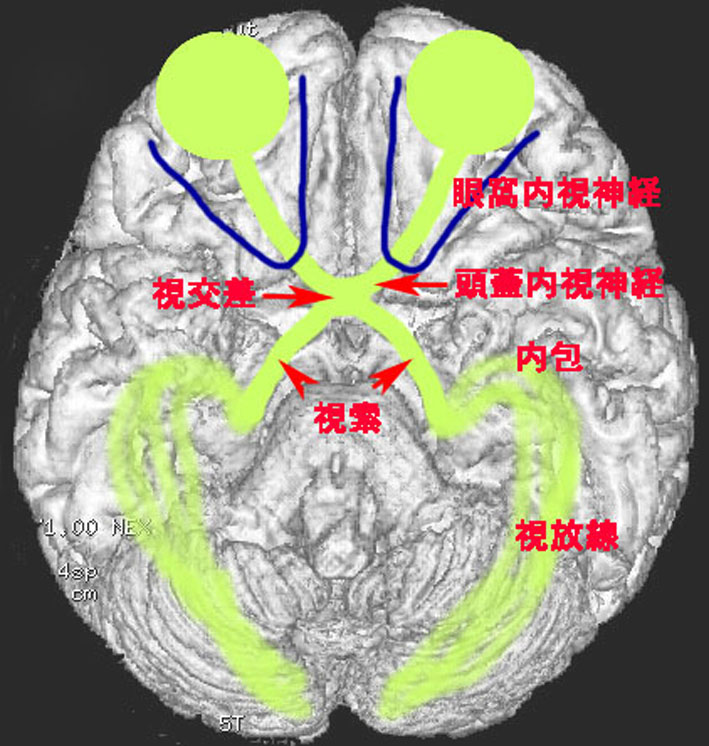

視路 optic pathwayの解剖学

- 視覚情報は,眼球網膜に入って,眼窩内の視神経を通って,頭蓋内に入ります

- 頭蓋内視神経はとても短いです

- 両側の視神経が交わる所を視交差とよびます

- 視交差からまた左右に分かれて,視索になります

- 視索は外側膝状体というところで脳の中に入ります

- そこからは内包後脚,視放線を伝わって,後頭葉まで行きます

- 視路毛様細胞性星細胞腫は上記のどこでも発生します

- この視路に沿って浸潤して広がります